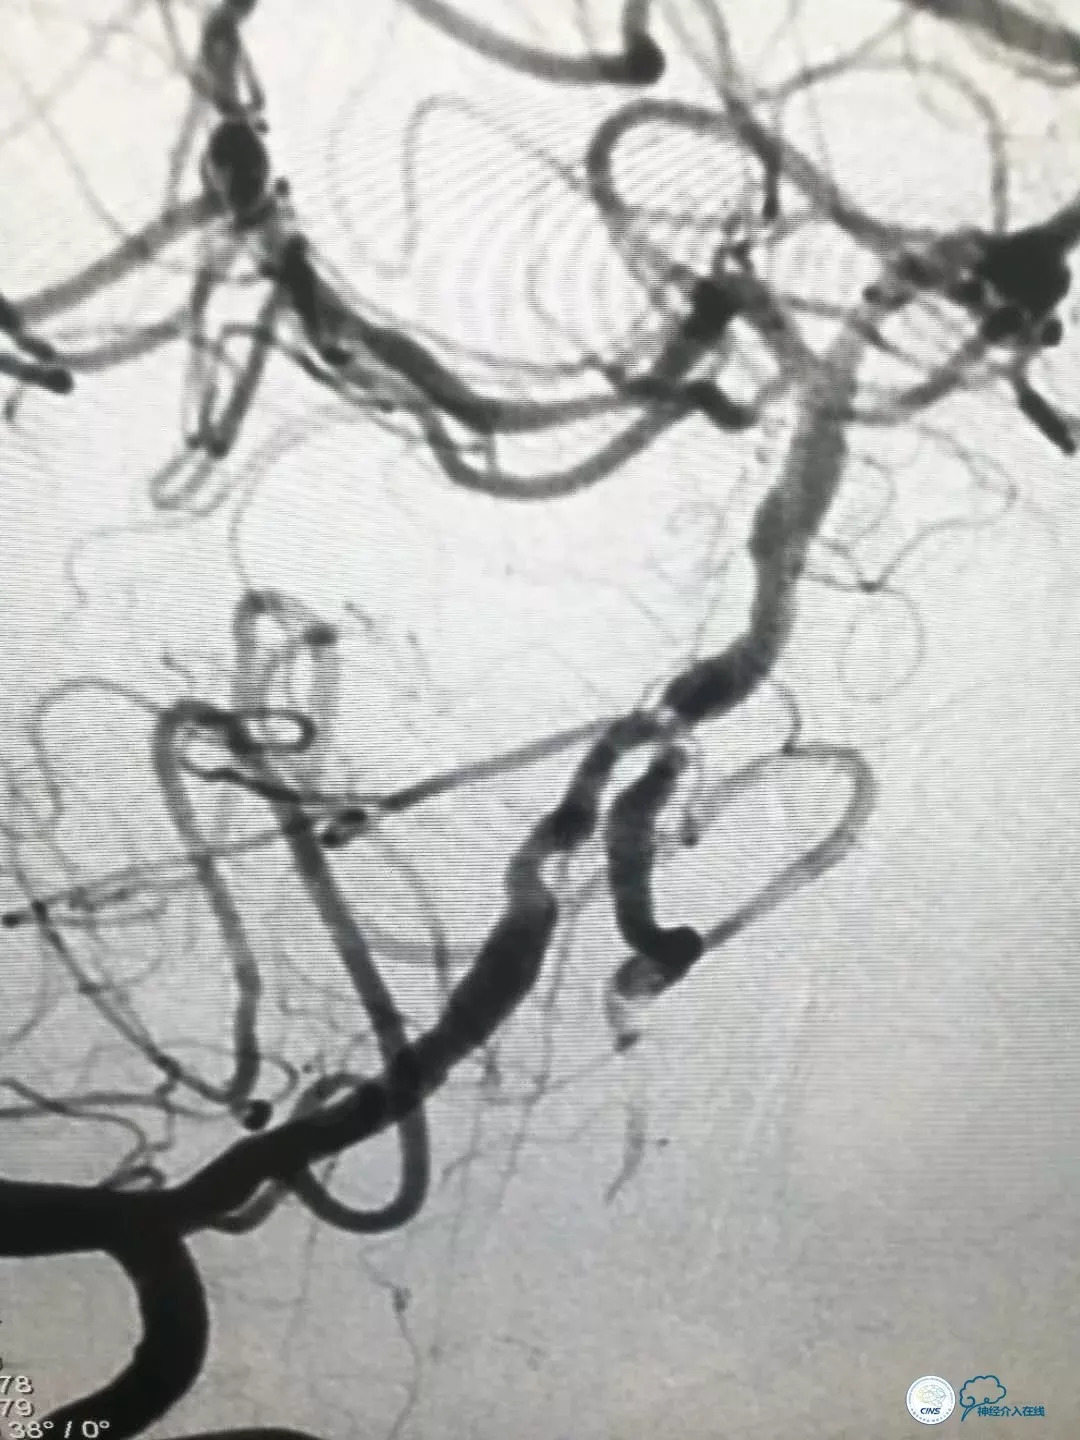

DSA提示: 右椎动脉V4段及基底动脉近端串联重度狭窄,左椎动脉开口迂曲,左椎动脉V4段重度狭窄,发出PICA后以远显影浅淡,左颈内动脉后交通段动脉瘤(2×2.5mm)(图4-8)。

全麻下右股动脉入路, 6F导引导管至右椎动脉V2段远端,术前造影示右侧椎动脉及基底动脉重度狭窄,局部可见充盈缺损,考虑斑块掀起(图9)。